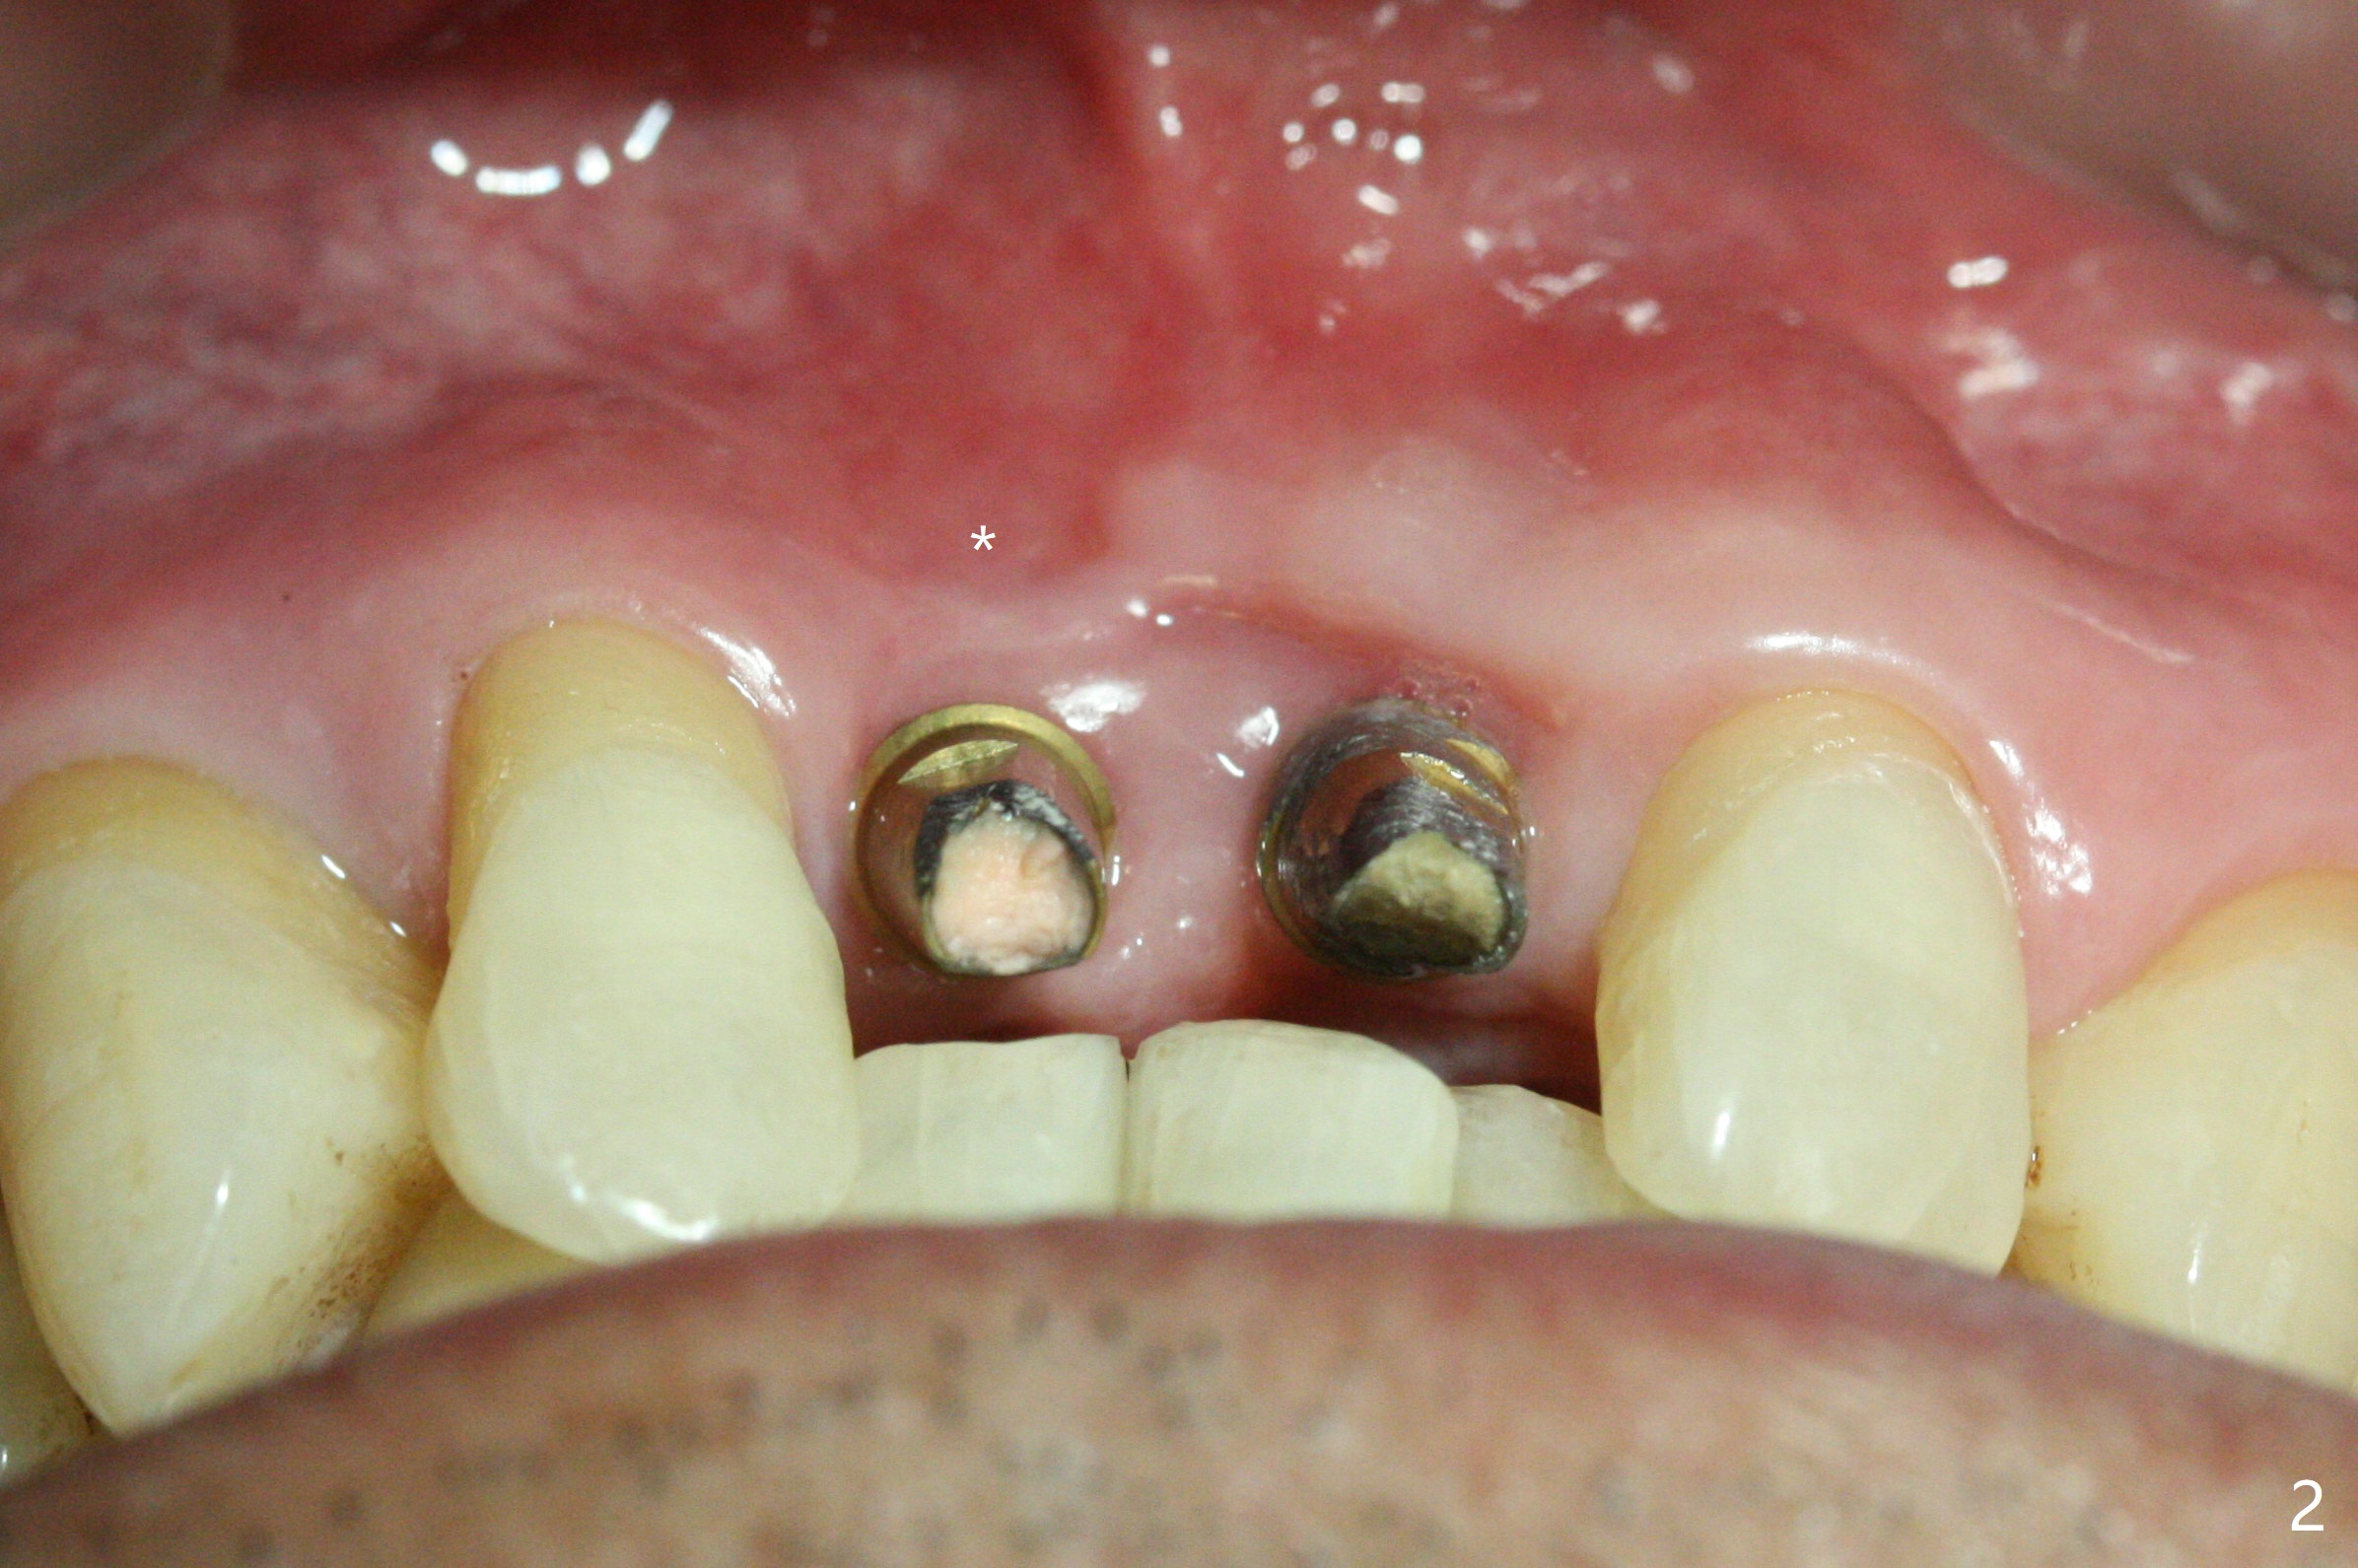

The gingiva remains recessive at #8 and 9 six months post immediate implant placement with bone graft (Fig.1). The buccal plate at #8 is particularly concave before (Fig.2 *) and after (Fig.3) abutment removal. The bony defect repair is assisted by placing a 4 mm tenting screw between the 2 implants (Fig.4) and placing allograft mixed with PRF (as putty) around the screw (Fig.5 (after replacement of the abutments)). The buccal contour improves because of the tenting screw and the bone graft placement (Fig.6 (as well as PRF and 6-month membranes)). The wound dehisces 12 days postop and immediately before leaving country for months (Fig.7). The sutures are removed, Osteogen plug is inserted (Fig.8) and periodontal dressing is applied (Fig.9). PA is taken to show the tenting screw (Fig.10 T). The latter is exposed 3 months postop (Fig.11,12). It appears that gingival graft is a must (Fig.13). Make a palatal stent, remove the temp with abutments and create a bleeding surface before harvesting a large piece of tissue. Connective tissue graft is done 5 months post bone graft (Fig.14). In fact there is no implant thread exposure. In fact the connective tissue graft does not survive. The abutments are re-prepared for pink porcelain (Fig.15). The bone loss is stable 1 year post cementation in spite of incomplete abutment seating (Fig.16). The soft tissue is nearly normal (Fig.17).